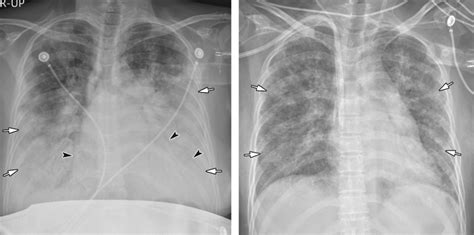

Đây là tình trạng ngạt thở do rất nhiều lý do các giai đoạn tiến triển của phù phổi cấp: Phù phổi do nguyên nhân tim mạch và phù phổi không do nguyên nhân tim mạch. Phù phổi cấp là một loại bệnh phổi cũng khá phổ biến. Bệnh viện chợ rẫy cần cung cấp thông tin thật sớm và chính xác xem việc phù phổi cấp có liên quan hay không mũi tim ngừa covid lần hai ? Nguyên nhân do tâm thất trái của tim bị suy nên không đẩy hết máu trong tuần hoàn phổi (phù phổi do tim). Người thầy thuốc phải hướng đến nguyên nhân và triệu chứng phù phổi khi điều trị bệnh nhân. Khi các tác nhân gây bệnh viêm phổi vượt qua hàng rào bảo vệ của cơ thể sẽ xâm nhập vào đường hô hấp. Chụp x quang phổi sẽ cho thấy các thâm nhiễm lan tỏa 2 bên như với hội chứng suy hô hấp cấp (ards) 5.

Phù phổi cấp là một dạng phổi chứa đầy dịch đột ngột đi vào túi khí bên trong gây ra hiện tượng khó thở. Chụp x quang phổi sẽ cho thấy các thâm nhiễm lan tỏa 2 bên như với hội chứng suy hô hấp cấp (ards) 5. Học nghe tiếng phổi trong bệnh lý phù phổi cấp tiếng phổi trong copd: Phù phổi cấp là tình trạng ứ dịch ở khoảng kẽ và phế nang. Adrs hiếm gặp nhưng tiên lượng rất xấu.